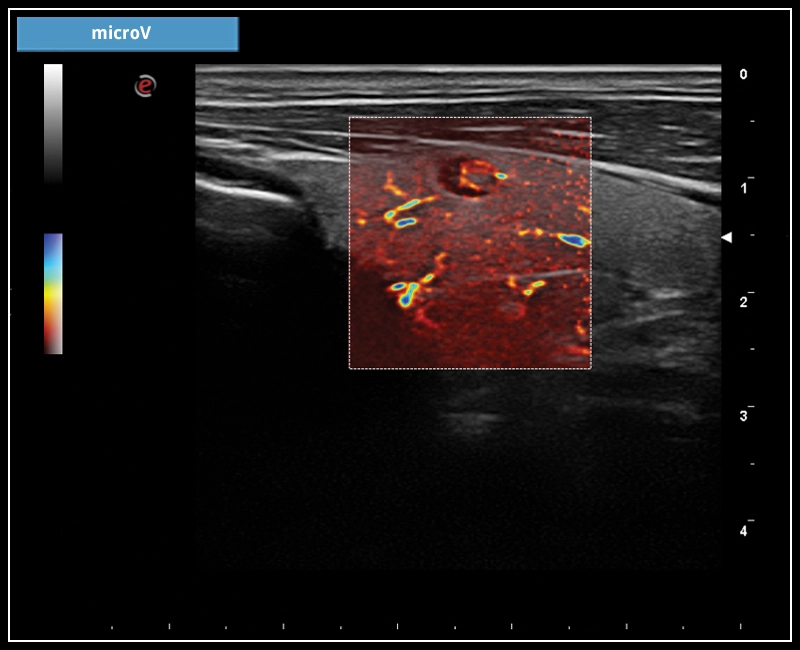

MyLab™X7 - microV

MyLab™X7 - microV